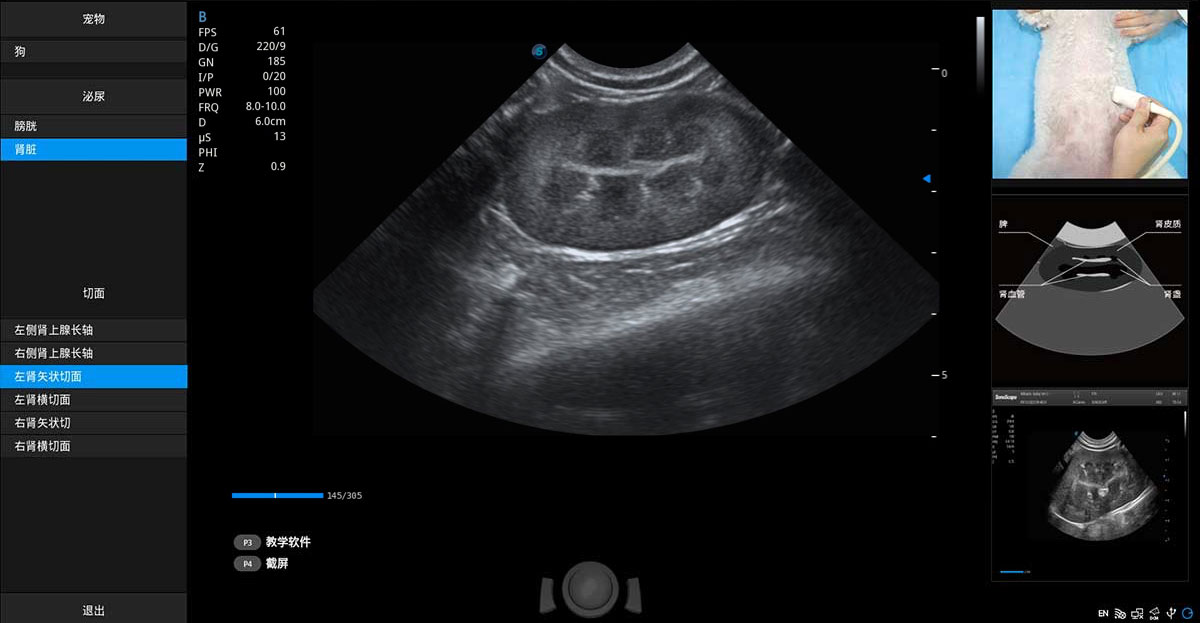

提供解剖示意圖、標(biāo)準(zhǔn)超聲圖像、掃查手法涂和操作者實時檢查圖像,指導(dǎo)操作者進(jìn)行標(biāo)準(zhǔn)切面的正確掃查。

ProPet 80 專為動物醫(yī)生設(shè)計,對不同的動物體型和生理結(jié)構(gòu)作出了針對性的優(yōu)化。通過動物影像專用軟件,可滿足個性化的應(yīng)用需求,幫助動物醫(yī)生獲得更精確的診斷數(shù)據(jù)。

ProPet 80 全新的動物超聲智能軟件和豐富的探頭群,為動物醫(yī)生提供了高清晰度和精細(xì)分辨率的圖像,無論在寵物、馬科、畜牧還是實驗室動物等應(yīng)用中都可以輕松應(yīng)對,為您的日常工作帶來滿意的體驗。